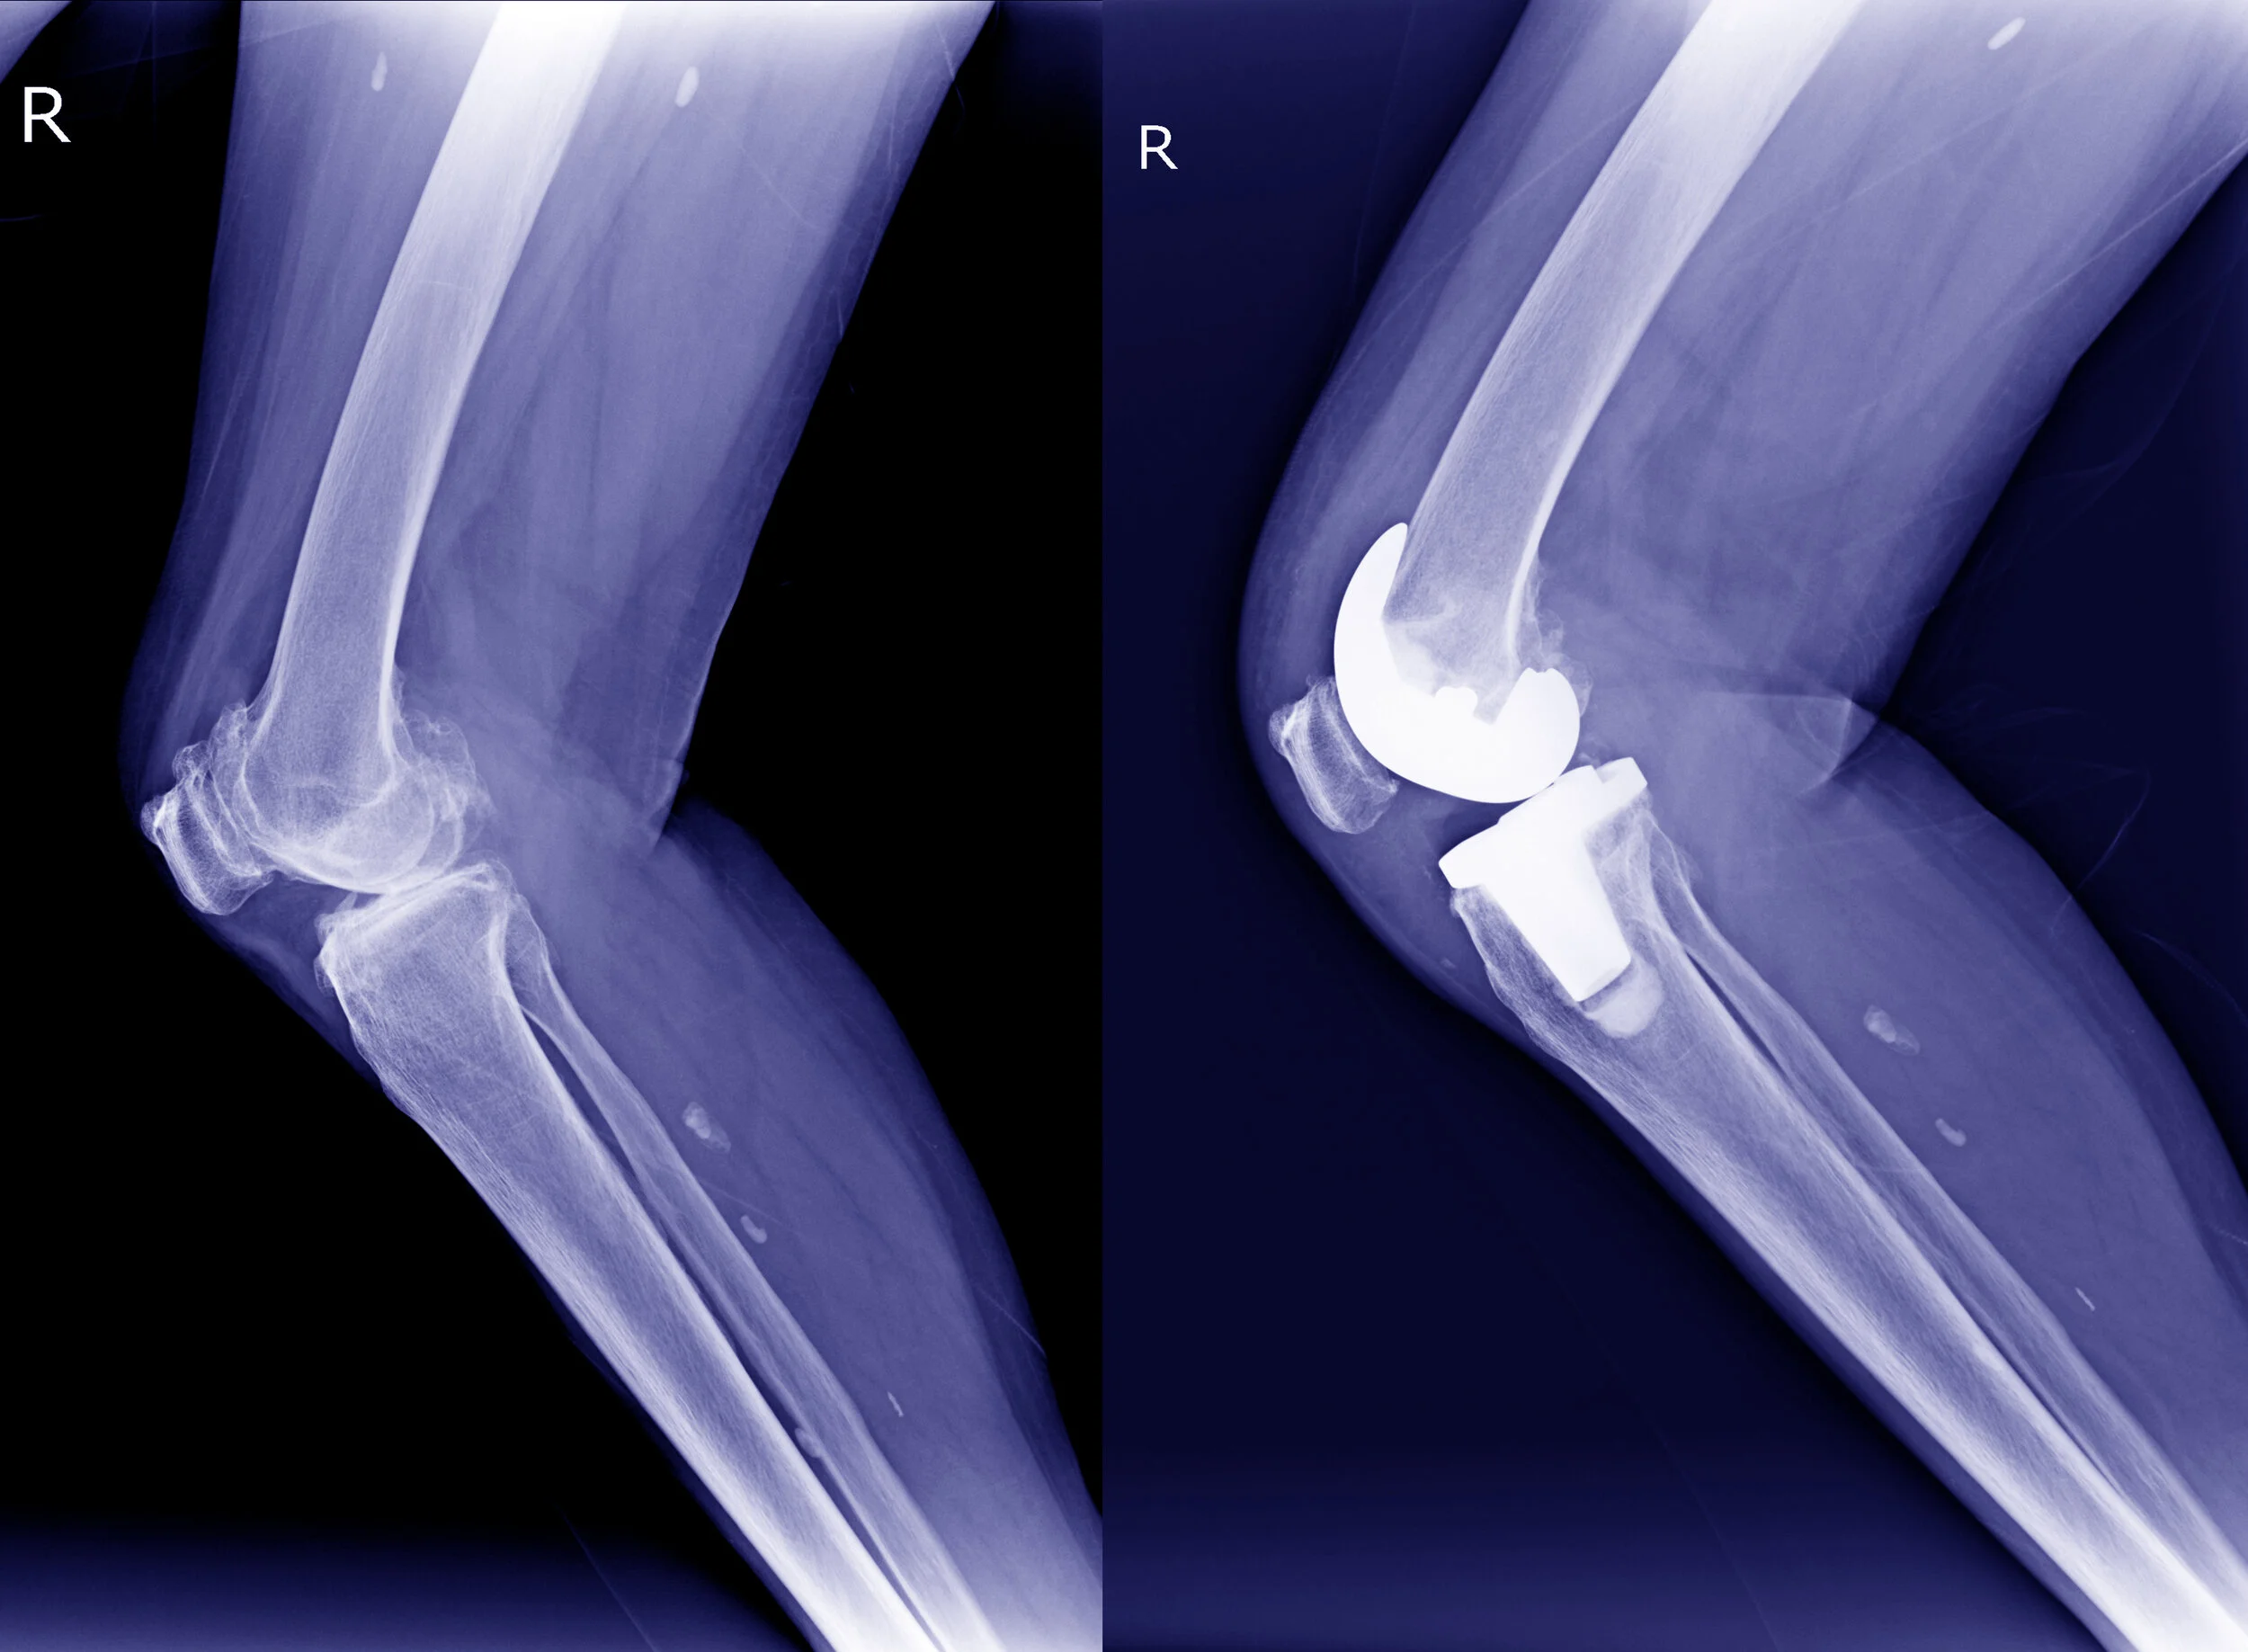

Röntgen Knie

Als erfahrener Kniegelenkschirurg an der Spezialabteilung für künstlichen Hüft- und Kniegelenksersatz im Orthopädischen Spital Speising, kann ich meinen PatientInnen ein weites Spektrum von schonenden, konservativen Behandlungen über die Kniegelenksarthroskopie, den minimalinvasiven Kniegelenksersatz (Knieprothese), bis zu komplizierten Revisionseingriffen und Wechseloperationen am Kniegelenk anbieten.

Ich verwende Knieprothesen auf dem neuesten Stand der Wissenschaft sowie moderne Hilfsmittel wie die individuelle präoperative Planung mittel MRT oder CT. Die passgenaue Implantation wird durch präzise Computernavigation zusätzlich erhöht. Dies ermöglicht im Vergleich zu den klassischen Operationsmethoden ein geringeres Gewebstrauma, weniger Blutverlust, kürzere OP-Dauer und raschere postoperativ Mobilisation. Um eine möglichst rasche Erholung nach der Operation zu gewährleisten arbeiten wir in Speising nach den Prinzipien des international bewährten Rapid-Recovery - Programms.

Meniskusrisse oder Knorpelschäden im Kniegelenk können arthroskopisch (minimalinvasive „Schlüssellochchirurgie“ mittels speziellem Kamerasystem) behandelt werden. Hierbei setze ich auf modernste OP-Methoden, um Ihnen eine möglichst rasche Rückkehr zu Ihren sportlichen Aktivitäten zu ermöglichen.

Die Abklärung von schmerzhaften Gelenksprothesen gehört zu meinem Spezialgebiet. Sollte im Falle einer schmerzhaften/lockeren Kniegelenksprothese ein neuerlicher Eingriff/eine Wechseloperation notwendig sein, sind  Sie bei mir als einem erfahrenen Endoprothetik-Experten an der Spezialabteilung für künstlichen Knie- und Hüftgelenksersatz im Spital Speising in besten Händen.